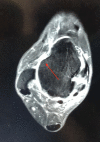

Pic 03: 3D reconstruction of 3D images of Tear

Further, we go for second opinion it is better in can of illusive ligament tears. However take a look at ligament tear seen in above images (Pic 01.02 and 03). They are copied from the paper submitted by Yan Xu to PMC. The order of images shows up clarity of the tear with better perspective. It might be good to have elementary 2D or 3D sequences but its very good to mimic the images in Isometric form. That is to create the 3D Models out of these 2D or 3D MRI Images. It takes involvement of senior radiologists and efforts to stitch up right images to reconstruct a  proper visual model that shall make sense to the viewer. PMC study indicated contrast between 3D MRI  with 2D MRI in diagnosing ATFL injury. The study took 45 patients with suspected ATFL injury. They were sent to conduct  MRI 2D and also taken 3D MRI sequences. The position was much made clear with extra efforts. Subsequently,  radiologist were asked  to  reconstruct ot to make 3D model of the body part. To test how accurate the result were, arthroscopic images from surgery were also checked.

The paper testifies that it would be rather efficient if the patient is advised to get 3D MRI reconstruction of suspected position to be made. The 3D reconstructed models can help the patients and surgeons to take the call for repair or further prognosis.